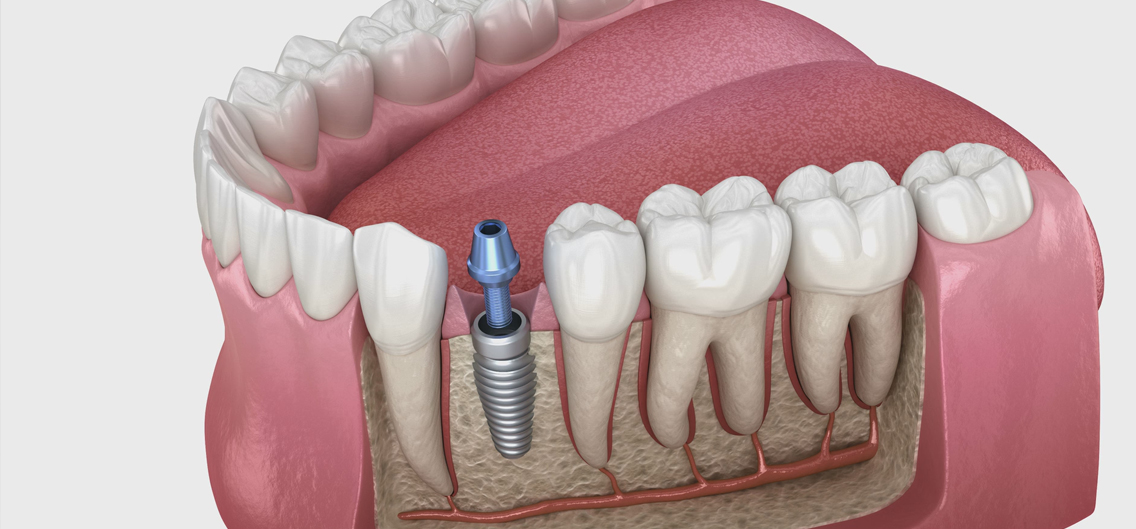

임플란트와 보철물을 이어주는 지대주를 부착하여 크라운을 올릴 기반을 마련합니다.

환자의 치아 모양·색상에 맞춰 맞춤 제작된 크라운을 부착해 자연스러운 심미성과 기능을 회복합니다.